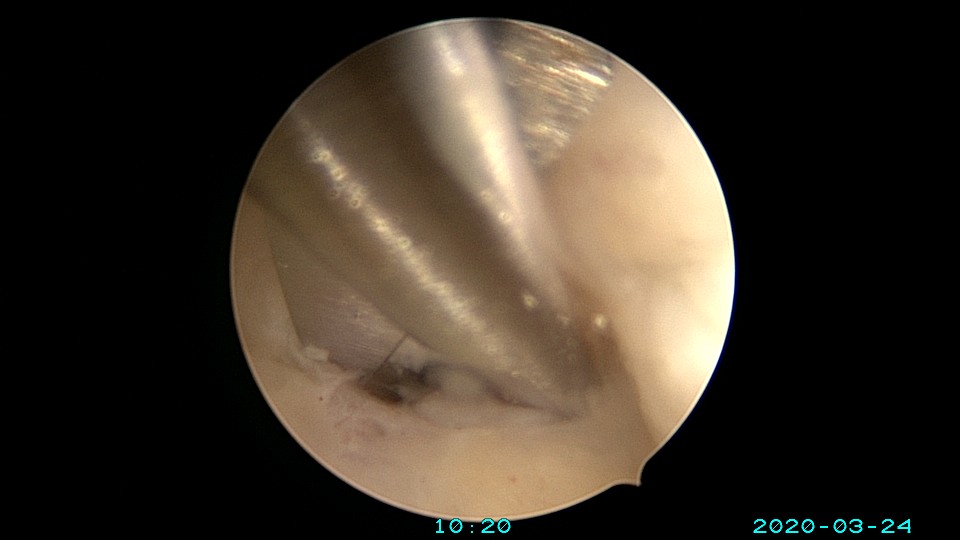

患者65岁,G1P1,顺产1次。安环30年,绝经10年。外阴白斑,阴道明显萎缩,无法置入扩阴器,阴道内镜方式找到宫颈外口,宫颈萎缩,穹隆几乎消失,无法夹持宫颈,宫颈管见多个息肉,宫颈内口狭窄坚硬,难以扩张。微型异物钳探查宫腔方向,用异物钳、微型剪刀扩大宫颈内口失败,改用双极电针切开宫颈内口,但镜子仍无法进入宫腔。用异物钳反复牵拉O型环至阴道内,中弯钳配合卵圆钳拉出节育环,环变形。有人问我何不用取环钩取环,这个病人探针和取环钩都无法发挥作用。